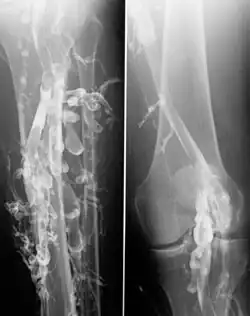

![]() Venography in a patient with deep vein thrombosis | |

Venography (also called phlebography or ascending phlebography) is a procedure in which an X-ray of the veins, a venogram, is taken after a special dye is injected into the bone marrow or veins. The dye has to be injected constantly via a catheter, making it an invasive procedure. Normally the catheter is inserted by the groin and moved to the appropriate site by navigating through the vascular system.

Contrast venography is the gold standard for judging diagnostic imaging methods for deep vein thrombosis; although, because of its cost, invasiveness, and other limitations, this test is rarely performed.[1]